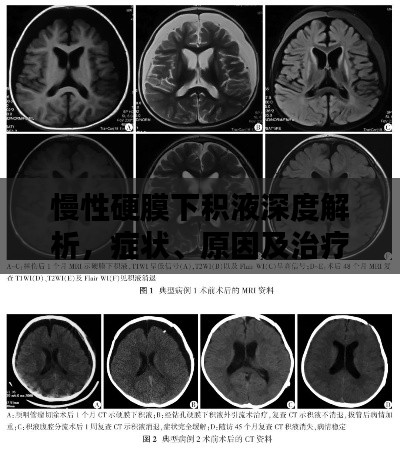

慢性硬膜下积液深度解析,症状、原因及治疗方法

在医学领域中,慢性硬膜下积液是一个相对常见的病症,本文将通过百度搜索,为您详细解析这一病症的相关知识。慢性硬膜下积液概述慢性硬膜下积液是指在硬脑膜下腔出现液体聚集的现象,这种病症通常表现为头痛、恶心、呕吐等症状,慢性...